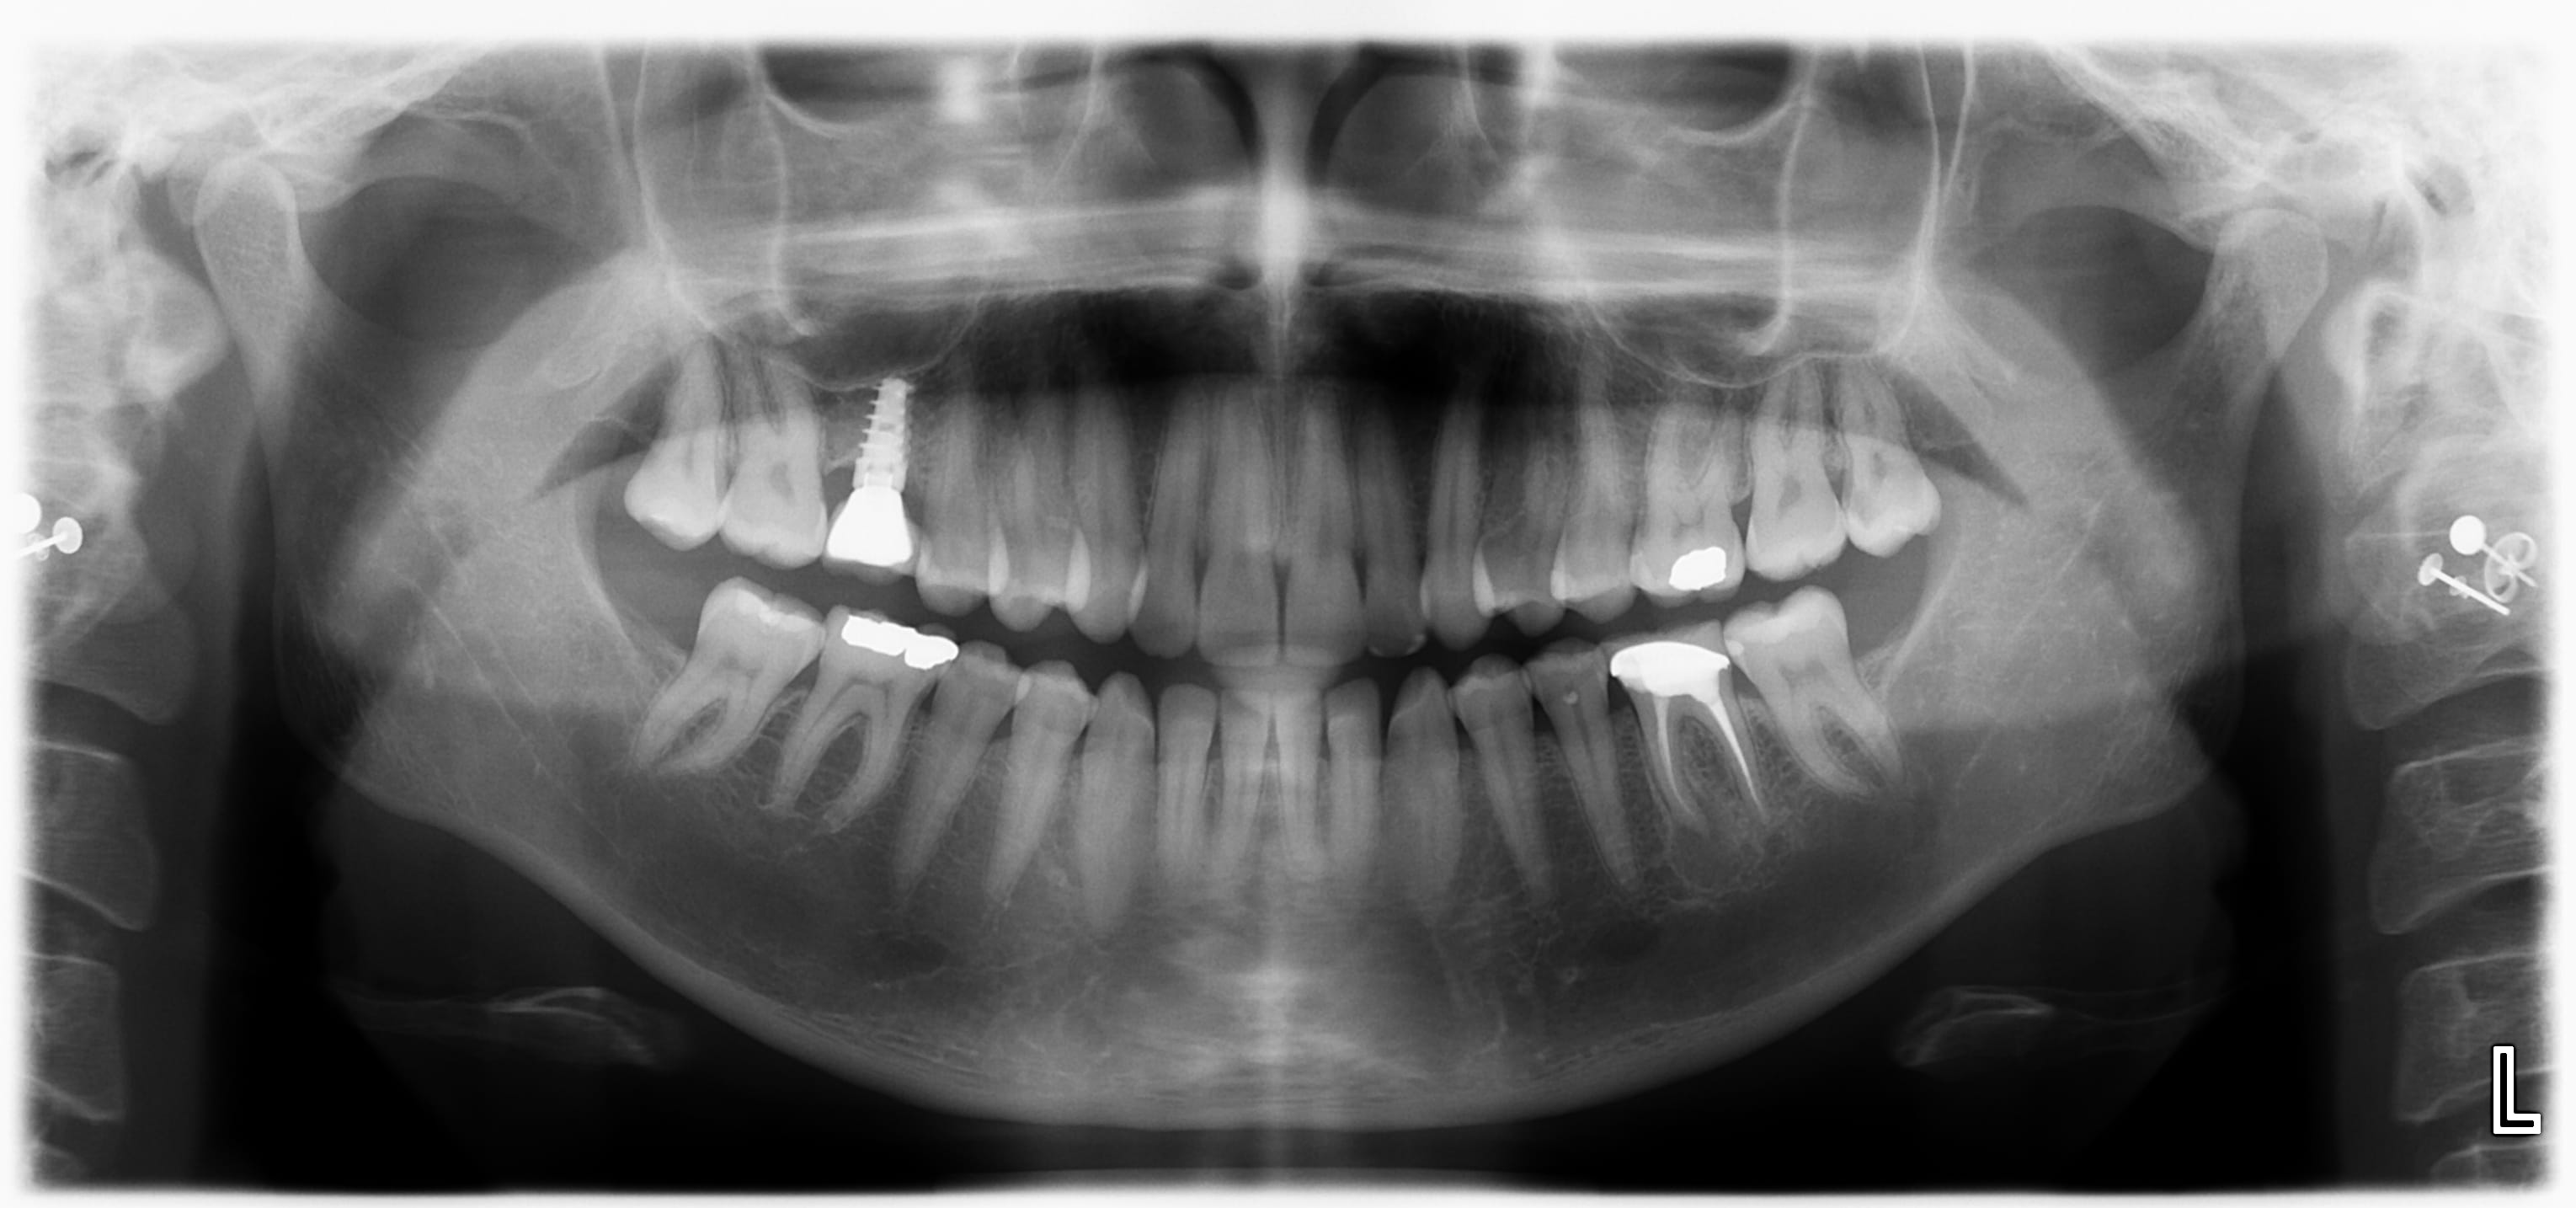

Une patiente se présente avec un implant AB Dental I5 4.5x10, posé en 2021, la couronne transvissée s'est déjà dévissée par deux fois.